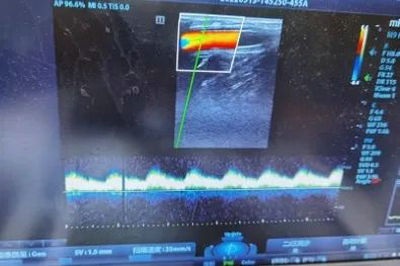

手术由崔文军主任医师主刀,安乾副主任医师和王梦宇住院医师配合。他们先在预先标记的的肘部做了一个3cm长的切口,顺利寻找到了拟进行搭桥的肱动脉和肱静脉,之后又在腕关节上方做了一个1cm长的纵切口,并应用隧道器完成了两个切口间的隧道构建。人工血管从隧道间通过,在前壁盘呈一个类椭圆形。通过仔细而耐心的缝合,人工血管的一头接到了肱动脉,另一头接到了肱静脉,手术顺利完成(图四)。术后3天后,床旁彩超检查提示上肢人工血管动静脉瘘血流通畅,流量达到了透析需求(图五)。医生为曹老爷子拔除了颈部的临时透析导管后,他顺利出院,回到当地进行规律透析,他对治疗的结果非常满意。

▲ 图五